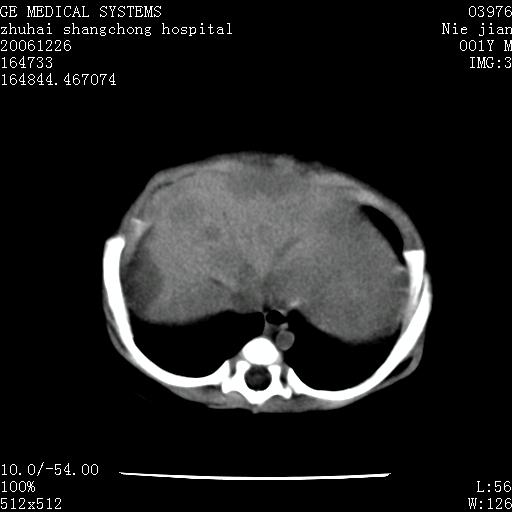

3个月婴儿腹胀来看。

肝各叶比率失调,明显增大,实质内大量脂肪侵润。另:左侧肾上腺区较大类圆形低密度肿块,左肾明显受压 下移。多考虑:1 左侧肾上腺神经母细胞瘤!2 肝弥漫性损伤!

肝各叶比率失调,明显增大,实质内见多发团块状低密度灶。另:左侧肾上腺区较大类圆形肿块,左肾明显受压 下移。多考虑:1 左侧肾上腺神经母细胞瘤!2 肝脏多发转移!

鉴别诊断:肾母细胞瘤,好发1-3岁,肾母细胞瘤是发生在肾脏,又称肾胚瘤,肾脏本身增大。而神经母细胞瘤也称成神经细胞瘤,好发1-2岁,多发生在肾上腺髓质。肾脏本身表现受压向下移位。

【影像特征】

1、肝明显增大,肝弥漫性低密度灶。

2、肾上腺区见类圆形肿块,其内密度不均,见片状偏高密度。

【诊断】

1、肝弥漫性病变,考虑急性肝炎致广泛脂肪浸润可能性大。

2、肾上腺区占位,假性肿瘤?肾上腺血肿(感染所致)?

1、关键着眼点:肝脏弥漫性病变内有没有走形的血管,仔细看部分低密度内有血管影(要有增强扫描作为证据就好了),说明并非肿瘤样病变,而是脂肪浸润。即可能不是转移瘤或原发肿瘤,低密度的形态上看,是片状,也不像肿瘤。

2、儿童肝炎最常见的是感染,有时食入性损害或药物也可致肝脏炎症,肝炎致大空泡型脂肪变性,是一种无痛性疾病,无症状,病因有营养异常、代谢性疾病、药物及病毒感染。所以脂肪变性与感染有关。

3、肝炎的结局是肝硬化,而恰恰一年后复查,已有肝硬化表现。肿瘤一般那会消失,那叫奇迹。

4、肾上腺出血也可见于败血症及感染,通常包块在数周内消失,ct表现包块内有偏高密度,可能是亚急性血肿的表现。假性肿瘤即腹部肠管积液、扩张血管及邻近结构的伪像。自然会消失。

5、因此,感染可以贯穿一切,解释一切。肿瘤自然消退?可能吗?那些应要无道理的创造奇迹的事情会那么容易发生吗?